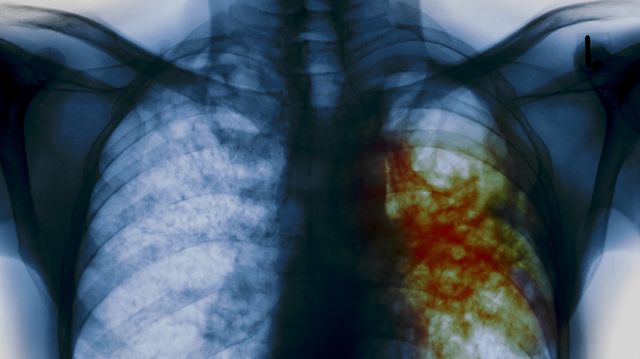

В Алапаевском районе вновь всплыла жуткая история, связанная с туберкулезом. Но на этот раз пострадать могли не коровы на ферме, а дети в школе, в которой полгода работал учитель с опасным заболеванием, перешедшим в открытую форму. Избежать эпидемии удалось лишь чудом, а родители узнали обо всем только после того, как у их детей тайно взяли кровь на анализ. Кроме того, до сих пор под угрозой находится здоровье троих педагогов и двоих детей.

На собрании местный фельдшер вместе с директором школы рассказали, что бывший учитель болеет открытой формой туберкулеза. Затем детям старше 15 лет пришлось пройти массово флюорографию, а остальным – сделать рентген легких. Кроме того, дети сдавали диаскинтест - более эффективный аналог пробы манту.

Ответ был получен с опозданием. В Алапаевской прокуратуре родителям сообщили, что после истории с заболевшим педагогом все его коллеги и ученики прошли обследование. У трех учителей и двух учеников была сомнительная реакция на тесты, и, хотя патологий пока не выявлено, их будут обследовать повторно через три месяца.

Сейчас ученики посещают школу в полном составе, очевидно, пока ни у кого не выявлена открытая форма туберкулеза. Но родителей это не успокаивает – неизвестно, что будет через полгода, ведь болезнь может проявиться позднее.